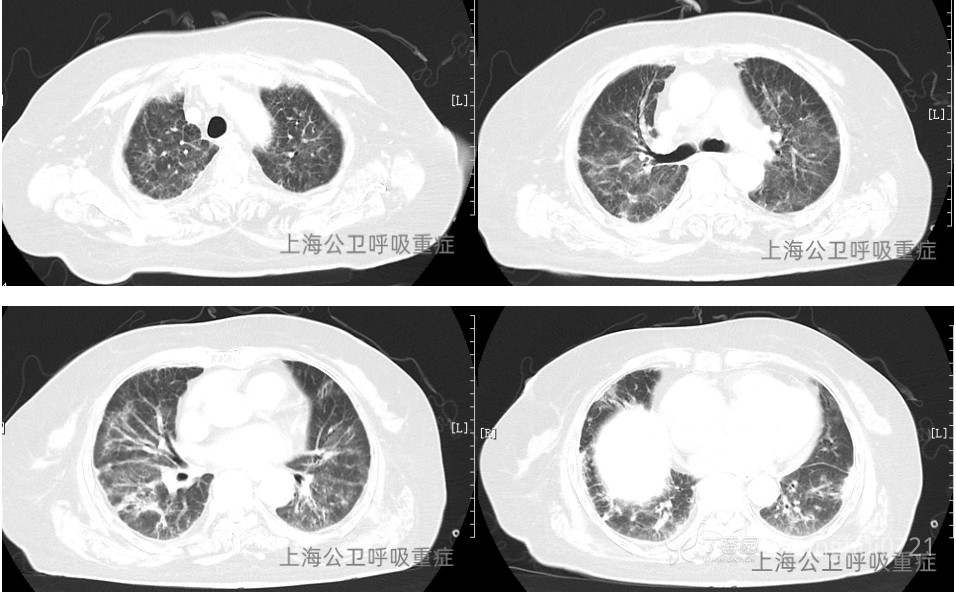

胸部CT:两肺散在多发炎症,合并间质性肺水肿可能,两侧少量胸腔积液,较前2022-7-28片明显好转,心脏增大,心包少量积液。(见图2)

图2